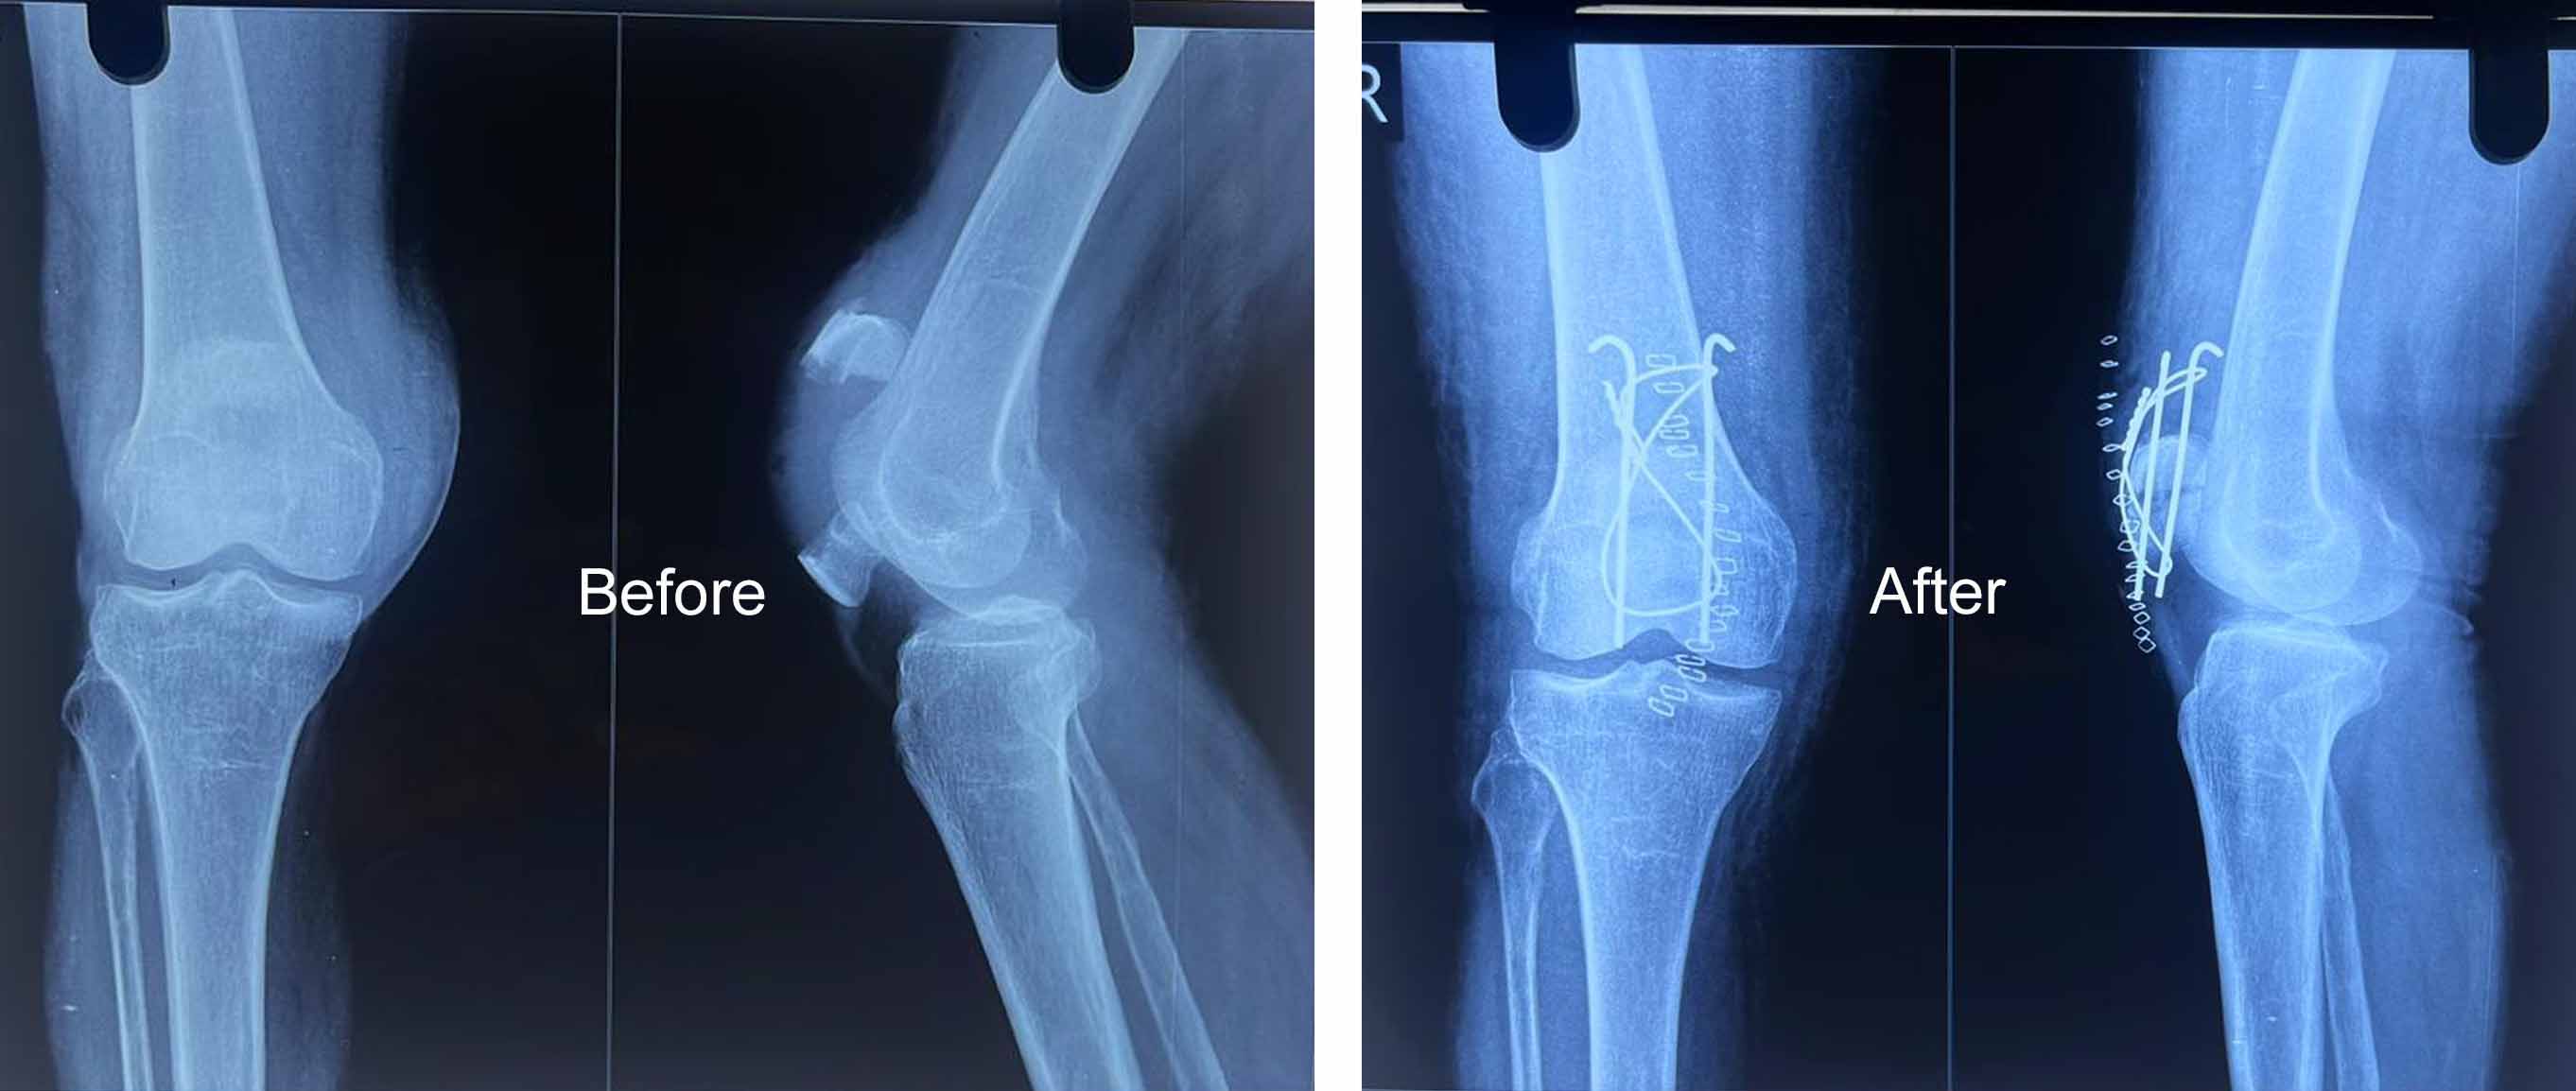

Medical Gallery

Orthopedic Care